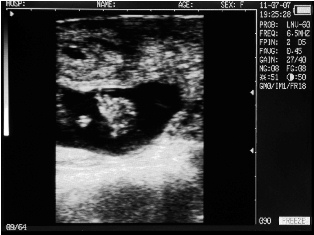

Ultrasound images of cows reproductive system, generated by a scanner Sonovet with rectal linear transducer.

Uterine horn heifers